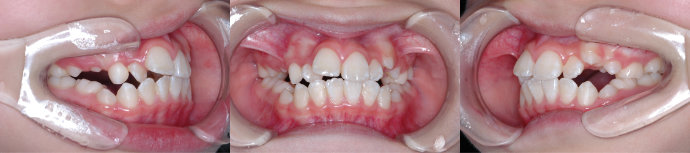

| Case7 |

| 前歯のガタガタ |

| <治療前> |

| <治療後> |

| 主訴 |

右上の前歯がねじれている |

| 診断名 |

叢生 |

| 年齢 |

8歳 |

| 使用装置 |

マルチブラケット装置 |

| 抜歯部位 |

永久歯の抜歯は無し |

| 治療期間 |

2年1か月 |

| 治療費概算 |

検査・診断料:5万円+税 装置・技術料:25万円+税 おおよそ1か月ごとの処置・管理料:5,000円+税 保定装置料:5万円+税 |

| リスク・副作用 |

特になし |